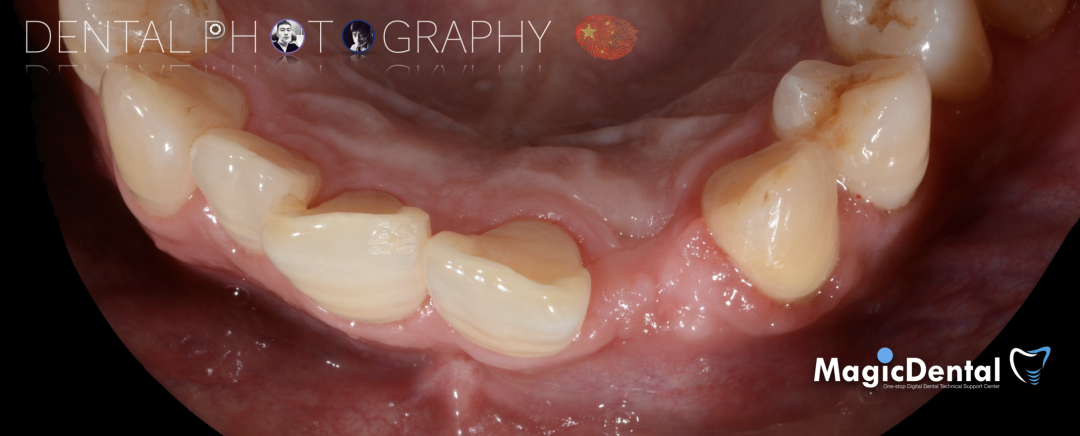

术后五个月复查及CBCT检查

制作种植导板,局麻下切开,翻瓣彻底暴露术区,取出骨钉。

导板就位,种植窝洞预备,植入Nobel Active 3.5*15mm种植体一枚,植入扭矩35N,安装临时基台。

口外制作树脂临时冠,抛光。安放树脂修复的临时冠,调整正中、前伸、侧方均无咬合干扰。

术后3个月CBCT及X线片。

术后三个月口内正面像

术前术后对比